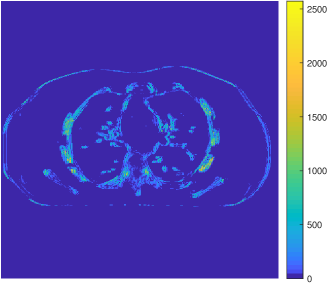

Figure 10: Reconstructions for ultra low-dose 2D scan simulated from raw measurements. The leftmost image is the PWLS-EP reconstructed image for the 200 mA200 mA200\text{ mA} scan. The second image is the PWLS-EP reconstruction for the simulated ultra low-dose scan, and it is the initial image for WavResNet [46], PWLS-ULTRA [38], and SPULTRA. The display windows are [800, 1400] HU.

Fig. 10 shows the reconstructions for the 200 mA200 mA200\text{ mA} scan (reference image) along with the reconstructions for the simulated ultra low-dose scan obtained with PWLS-EP, WavResNet, PWLS-ULTRA, and SPULTRA. Visually, WavResNet fails to reconstruct the image but improves over the initial PWLS-EP reconstruction, while PWLS-ULTRA and SPULTRA provide better image quality. This indicates that the ULTRA-based methods may have a better generalization property than WavResNet, since they learn more fundamental features of CT images (also see [38]). We selected three smooth ROIs, where the pixel values are approximately constant. Tab. V(b) shows the mean and the standard deviation of pixel values for these ROIs for various methods and the standard-dose reference. Since the iterative RNN version of WavResNet only has small improvements over PWLS-EP, the pixel values do not change much compared with PWLS-EP. PWLS-ULTRA however reduces the bias in the central region of the image (ROI 2), but fails to correct the bias in the regions near the bones (ROI 1 and ROI 3). SPULTRA reduces the bias in the central region of the image, and also significantly corrects the bias near the bone regions. The standard deviations of the ROIs reconstructed by SPULTRA are comparable to those reconstructed by PWLS-ULTRA, and are close to those of the reference ROIs. Additionally, SPULTRA reconstructs the bone (indicated by the magenta arrow in the last two subfigures of Fig. 10) better than PWLS-ULTRA.